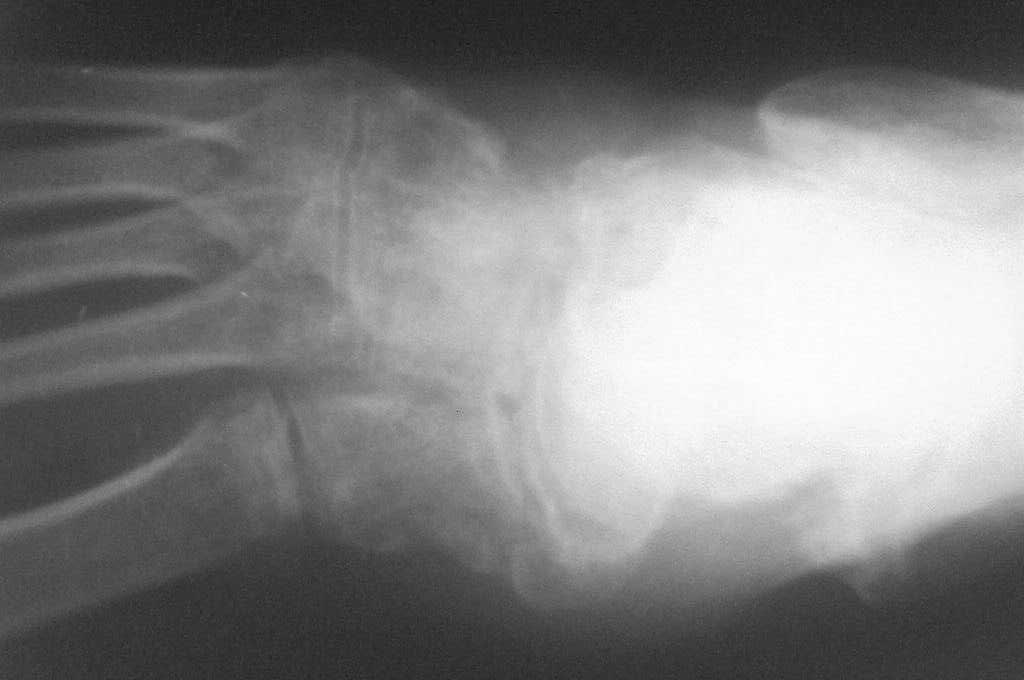

Обратился  больной  46 лет. 3 месяца  назад  получил  травму  левой

стопы в  результате  ДТП, живет в  отдаленный  степной  зоне, лечился

у  местного  табиба. Ходит при  помощи двух  костылей, наступая на

пятку, на  передний  отд.  стопы  наступать  не  может  из-за боли,

умеренная  отечность  стопы и  деформация в  обл ладьевидной кости,

движения  в  голеностопном суставе в  польном  обьеме, в среднем

отд.  ограничены  и  болезненны.